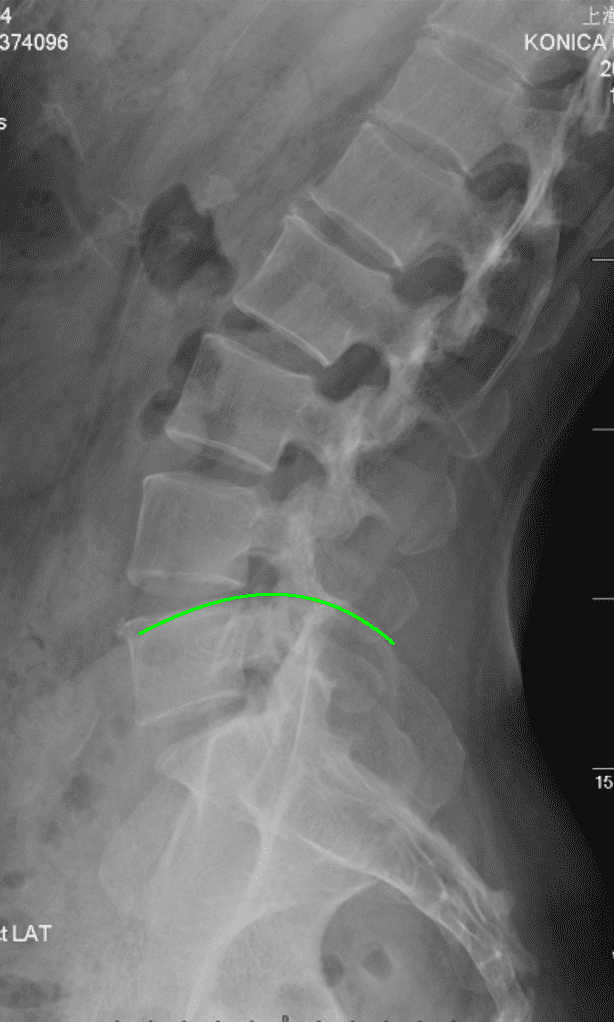

椎骨 / 髂骨 精确标记例

将传统通过点标记训练的 UNet 峰值 22 通道分类模型 + UNet ROI 窗口粗分割模型 替换为对线性顺序和先验顺序更精确的 HRNet 模型,识别率提高并且对于复杂情况的识别能力大幅提升。

将 UNet 训练的髂脊线识别模型(UNet 只适合进行分割,对于线段识别定位预测为概率热图,并不方便进行线段化)替换为 VGG16-BN 专注于线段提取。